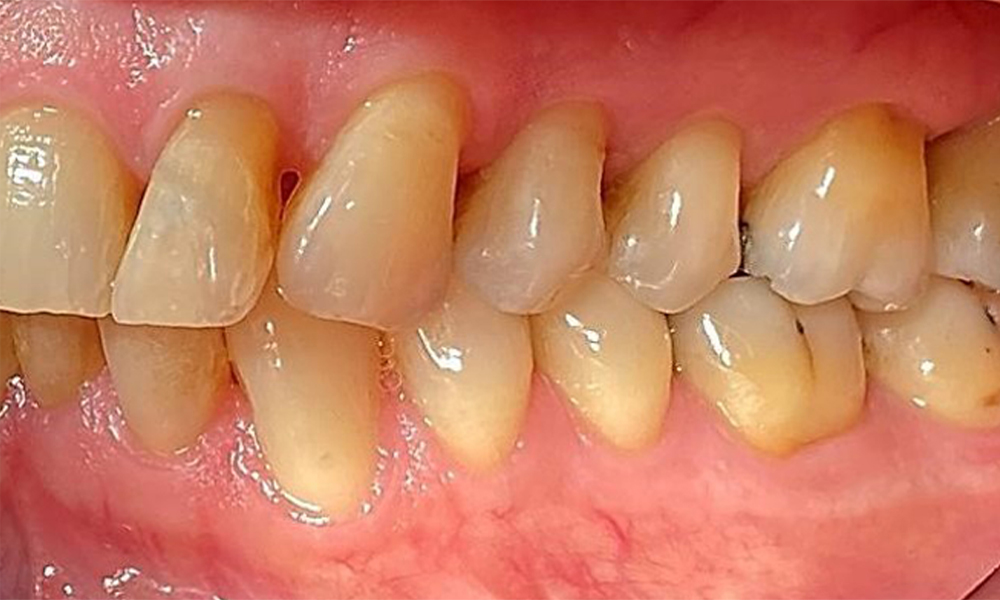

Right lateral view. Loss of the interdental papillae.

Fig. 3 Right lateral view. Loss of the interdental papillae. © Dr R. Krapf

Left lateral view including the recessions.

Fig. 4 Left lateral view including the recessions. © Dr R. Krapf

The patient has a full dentition with 28 teeth, which includes amalgam and composite fillings in the molar and premolar regions. There is a visible clinical marginal gap present on tooth 14. Tooth 27 has an adequate gold inlay. There are also generalized attritions and abrasions. (Fig. 2, Fig. 3, Fig. 4, Fig. 5, Fig. 6)

The patient has stage II, grade B periodontitis (5). At 1 to 3 mm, the clinical probing depths were within the physiological range. Localized probing depths of 5 mm were observed on the mesiopalatal aspects on both 17 and 27. There are generalized recessions of 1–3 mm with partial loss of the interdental papillae (Fig. 2, Fig. 3, Fig. 4)